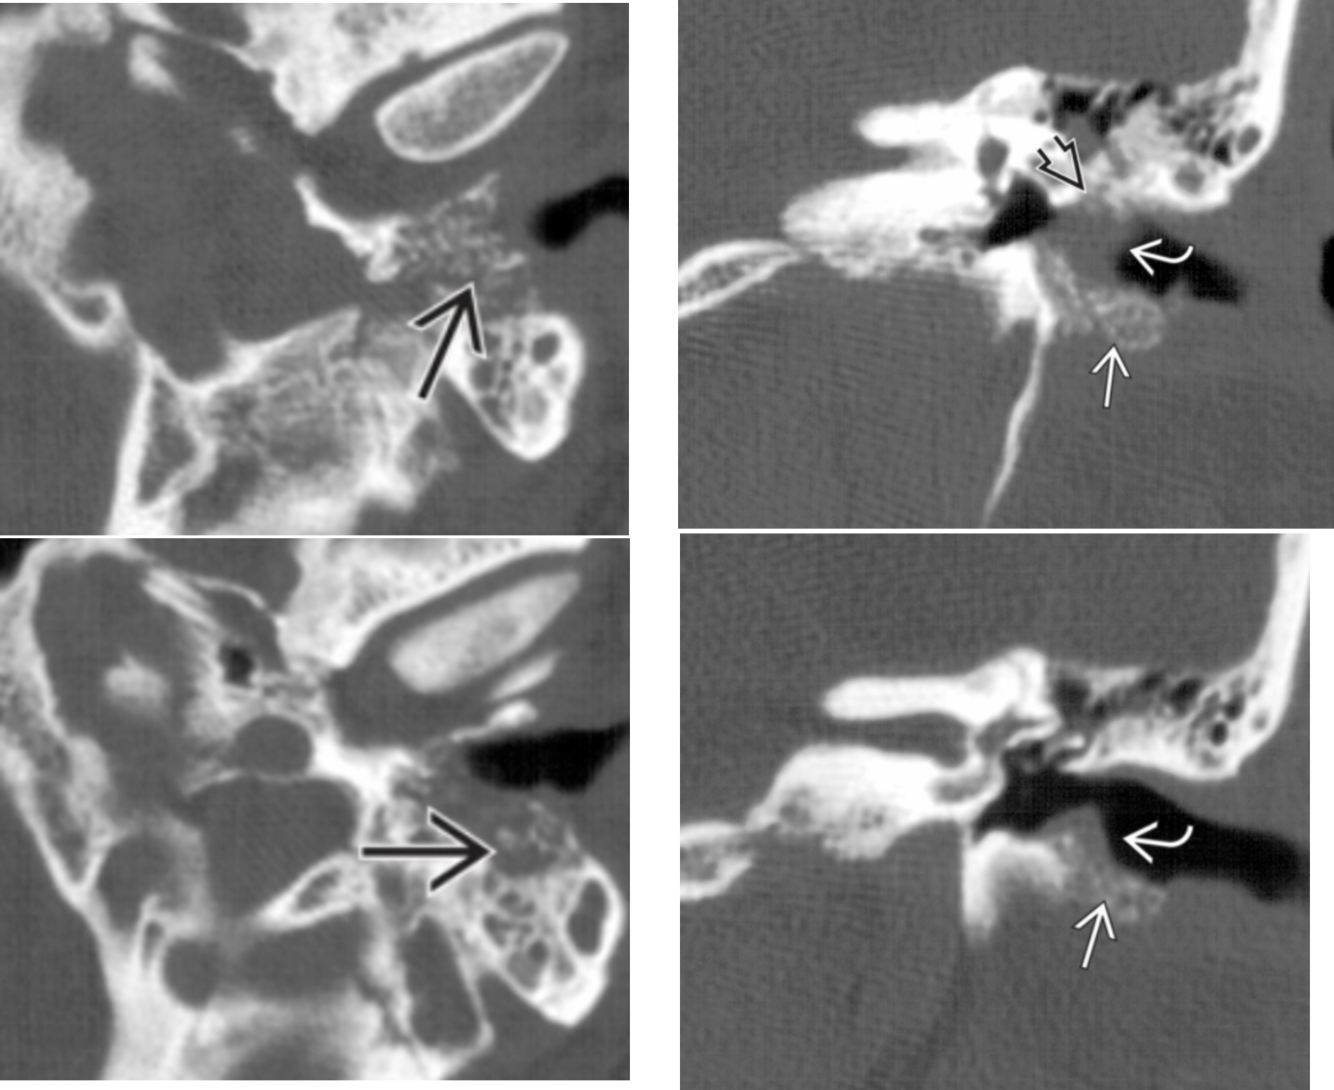

Prolapsing facial nerve (protruding intratemporal facial nerve)

Tubular soft tissue prolapsing into oval window niche from undersurface of LSC. Caused by dehiscence of bony covering of the facial nerve.

No enhancement! If enhances then it is a Schwannoma.

May project into oval indow.